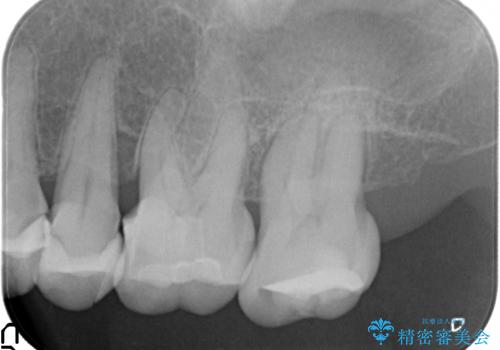

歯ぎしりに抵抗する歯周補綴 インプラント補綴

- 朝起きると歯が痛く歯ぎしり、歯の揺れの改善を求めて来院されました。

噛み合わせ・歯ぎしりにより、歯周病を発症し感染のコントロール、強い咬合力のコントロールをできるような補綴計画をたてます。

分岐部病変を併発していた歯は、抜歯としインプラントによる咬合機能の回復。残すことのできる歯は歯周治療後連結補綴を行い歯ぎしりに対抗します。